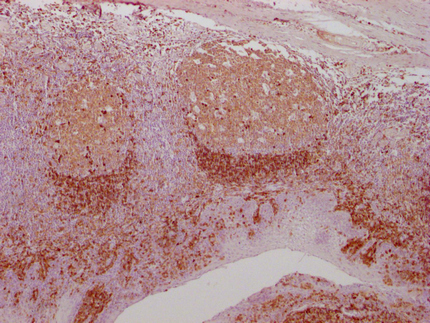

IHC image of CSB-MA961575 diluted at 1:100 and staining in paraffin-embedded human tonsil tissue performed on a Leica BondTM system. After dewaxing and hydration, antigen retrieval was mediated by high pressure in a citrate buffer (pH 6.0). Section was blocked with 10% normal goat serum 30min at RT. Then primary antibody (1% BSA) was incubated at 4°C overnight. The primary is detected by a Goat anti-mouse IgG polymer labeled by HRP and visualized using 0.05% DAB.